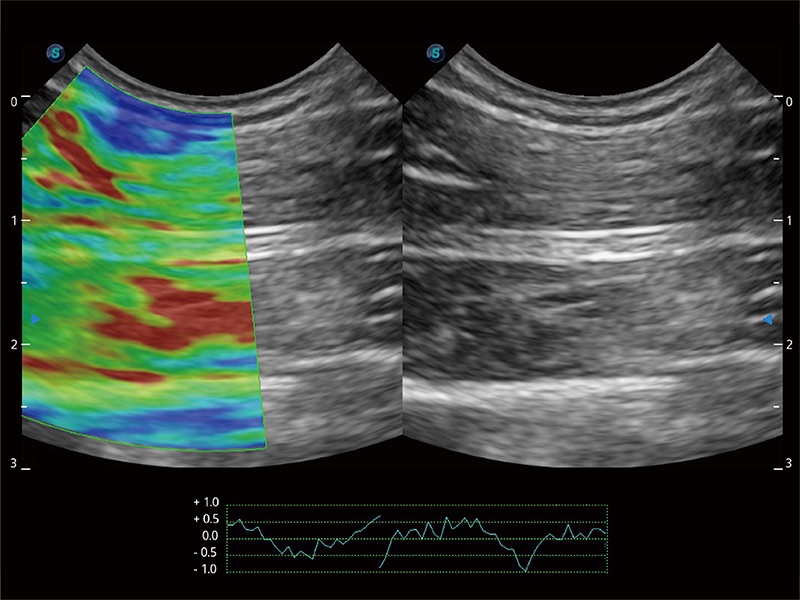

Nutzt myokardiale Doppler-Frequenzverschiebungen zur Quantifizierung der myokardialen Gewebebewegung, wobei Rot und Blau die unterschiedlichen Bewegungsrichtungen der Herzwände darstellen. Durch die Kombination von TDI und PW lässt sich die Bewegungsbahn der Myokardwand besser erfassen.